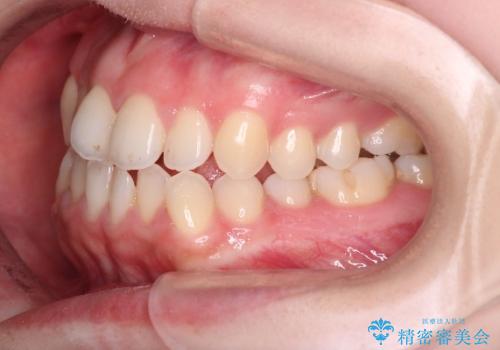

【オープンバイト】前歯のがたがたをなおしたい。

- 笑った時の前歯の見た目が気になることを主訴に来院されました。

上の歯が下の前歯を少し隠すぐらいを目指し、インビザラインにて治療を行いました。